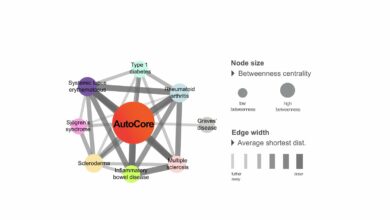

Abordagens baseadas em rede abrem um novo caminho para classificar e tratar doenças raras

O AutoCore e doenças autoimunes e autoinflamatórias poligênicas comuns. Esta figura ilustra a posição relativa do AutoCore no contexto dos…